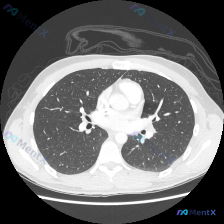

双肺多发微小结节,随机分布——如何一步步排查病因?

整理了一份胸部CT病例,和大家分享分析思路。 病例信息: 胸部CT肺窗横断面(心室水平上方,隆突以下,心脏轮廓可见)显示: - 双肺整体透亮度基本对称,无大片实变、磨玻璃影或空洞 - 气道通畅,无管壁增厚/狭窄 - 胸膜光滑,无胸腔积液/增厚 - 胸廓对称,胸壁软组织无异常 - 异常表现:双肺多处(...